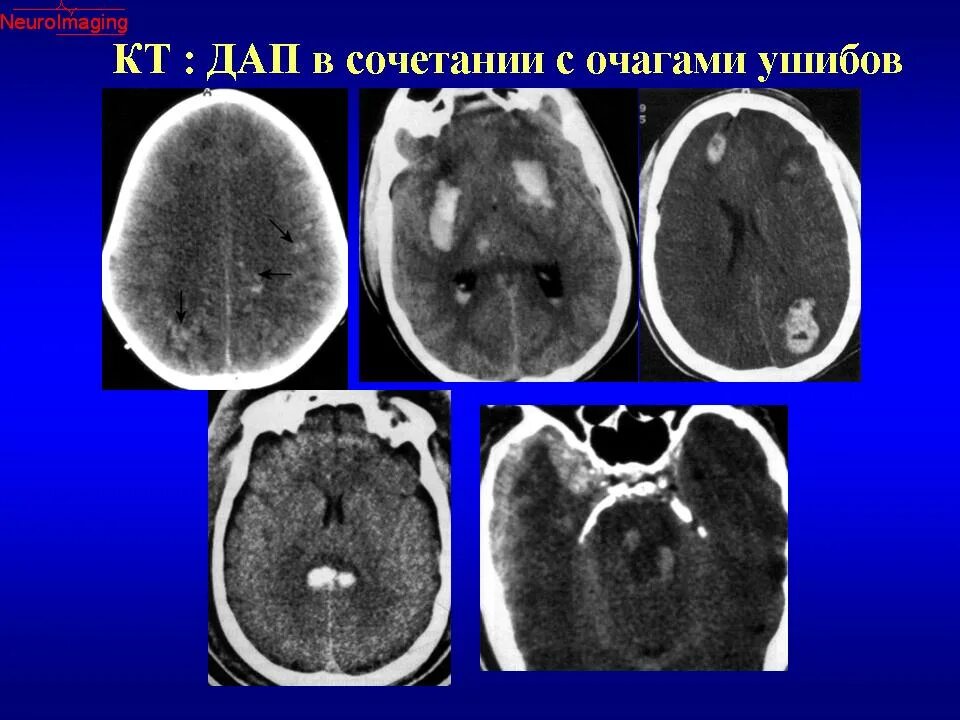

Диффузные повреждения